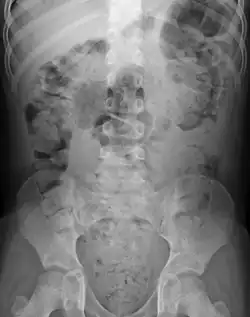

Abdominal X-rays are generally only performed if bowel obstruction is suspected, may reveal extensive impacted fecal matter in the colon, and may confirm or rule out other causes of similar symptoms.[26][17]